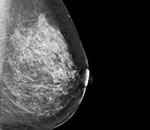

Рак молочной железы – это одно из самых распространенных онкологических заболеваний в мире. Этот термин объединяет сразу несколько видов опухолей, которые развиваются из разных тканей.

Рак груди — это ужасный диагноз, столкнуться с которым может каждая женщина. На ранних стадиях развития рак можно остановить, не прибегая к удалению молочной железы. Регулярный самоосмотр и посещение маммолога могут спасти не только красоту, но и жизнь.

Посещение маммолога – такое же важное профилактическое мероприятие для здоровья женщины, как и консультация гинеколога. Новообразования молочной железы всегда являлись актуальной проблемой женской онкологии. За последние годы заболеваемость раком груди ув